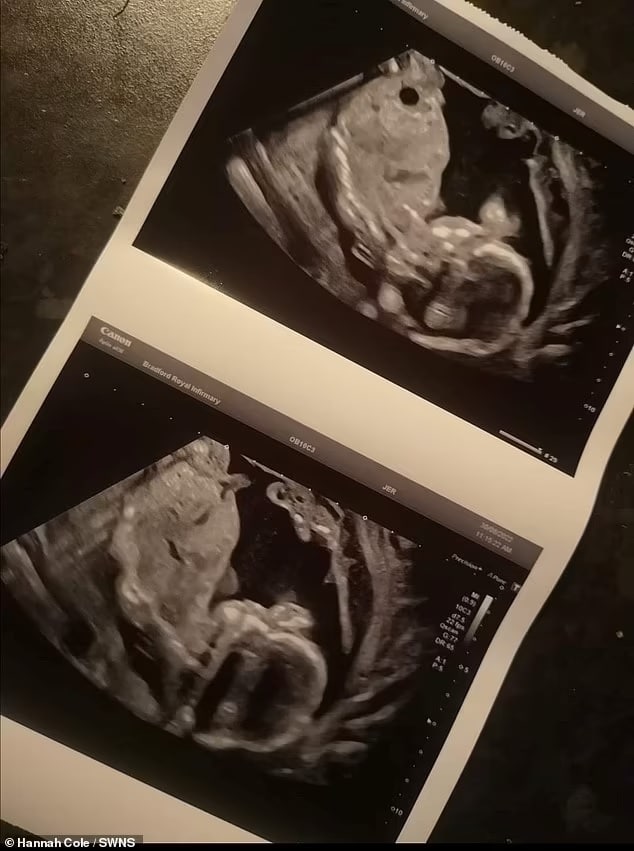

Hannah Cole, 27, foi internada no Bradford Royal Infirmary (BRI), na Inglaterra, depois que sua bolsa estourou prematuramente, com 20 semanas de gestação.

Os médicos disseram a ela no dia seguinte que o bebê havia morrido, depois que eles não conseguiram detectar um batimento cardíaco e reservaram Hannah para um parto induzido.

Mas o ‘instinto’ de que seu filho ainda estava vivo encorajou Hannah a pedir ao hospital um exame final – foi quando os médicos encontraram um batimento cardíaco e cancelaram o parto do suposto natimorto.

Oakley Cole-Fowler finalmente nasceu com apenas 24 semanas e três dias em 30 de outubro – pesando 780 gramas.